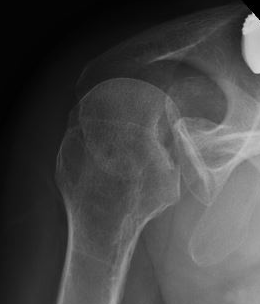

AP Xray

Abnormal overlap of humeral head on glenoid

Light-bulb sign - globular head secondary to internal rotation of the humeral head

Vacant Glenoid Cavity - > 6 mm space between humeral head and anterior rim of glenoid

Posterior shoulder dislocation

Posterior shoulder dislocations